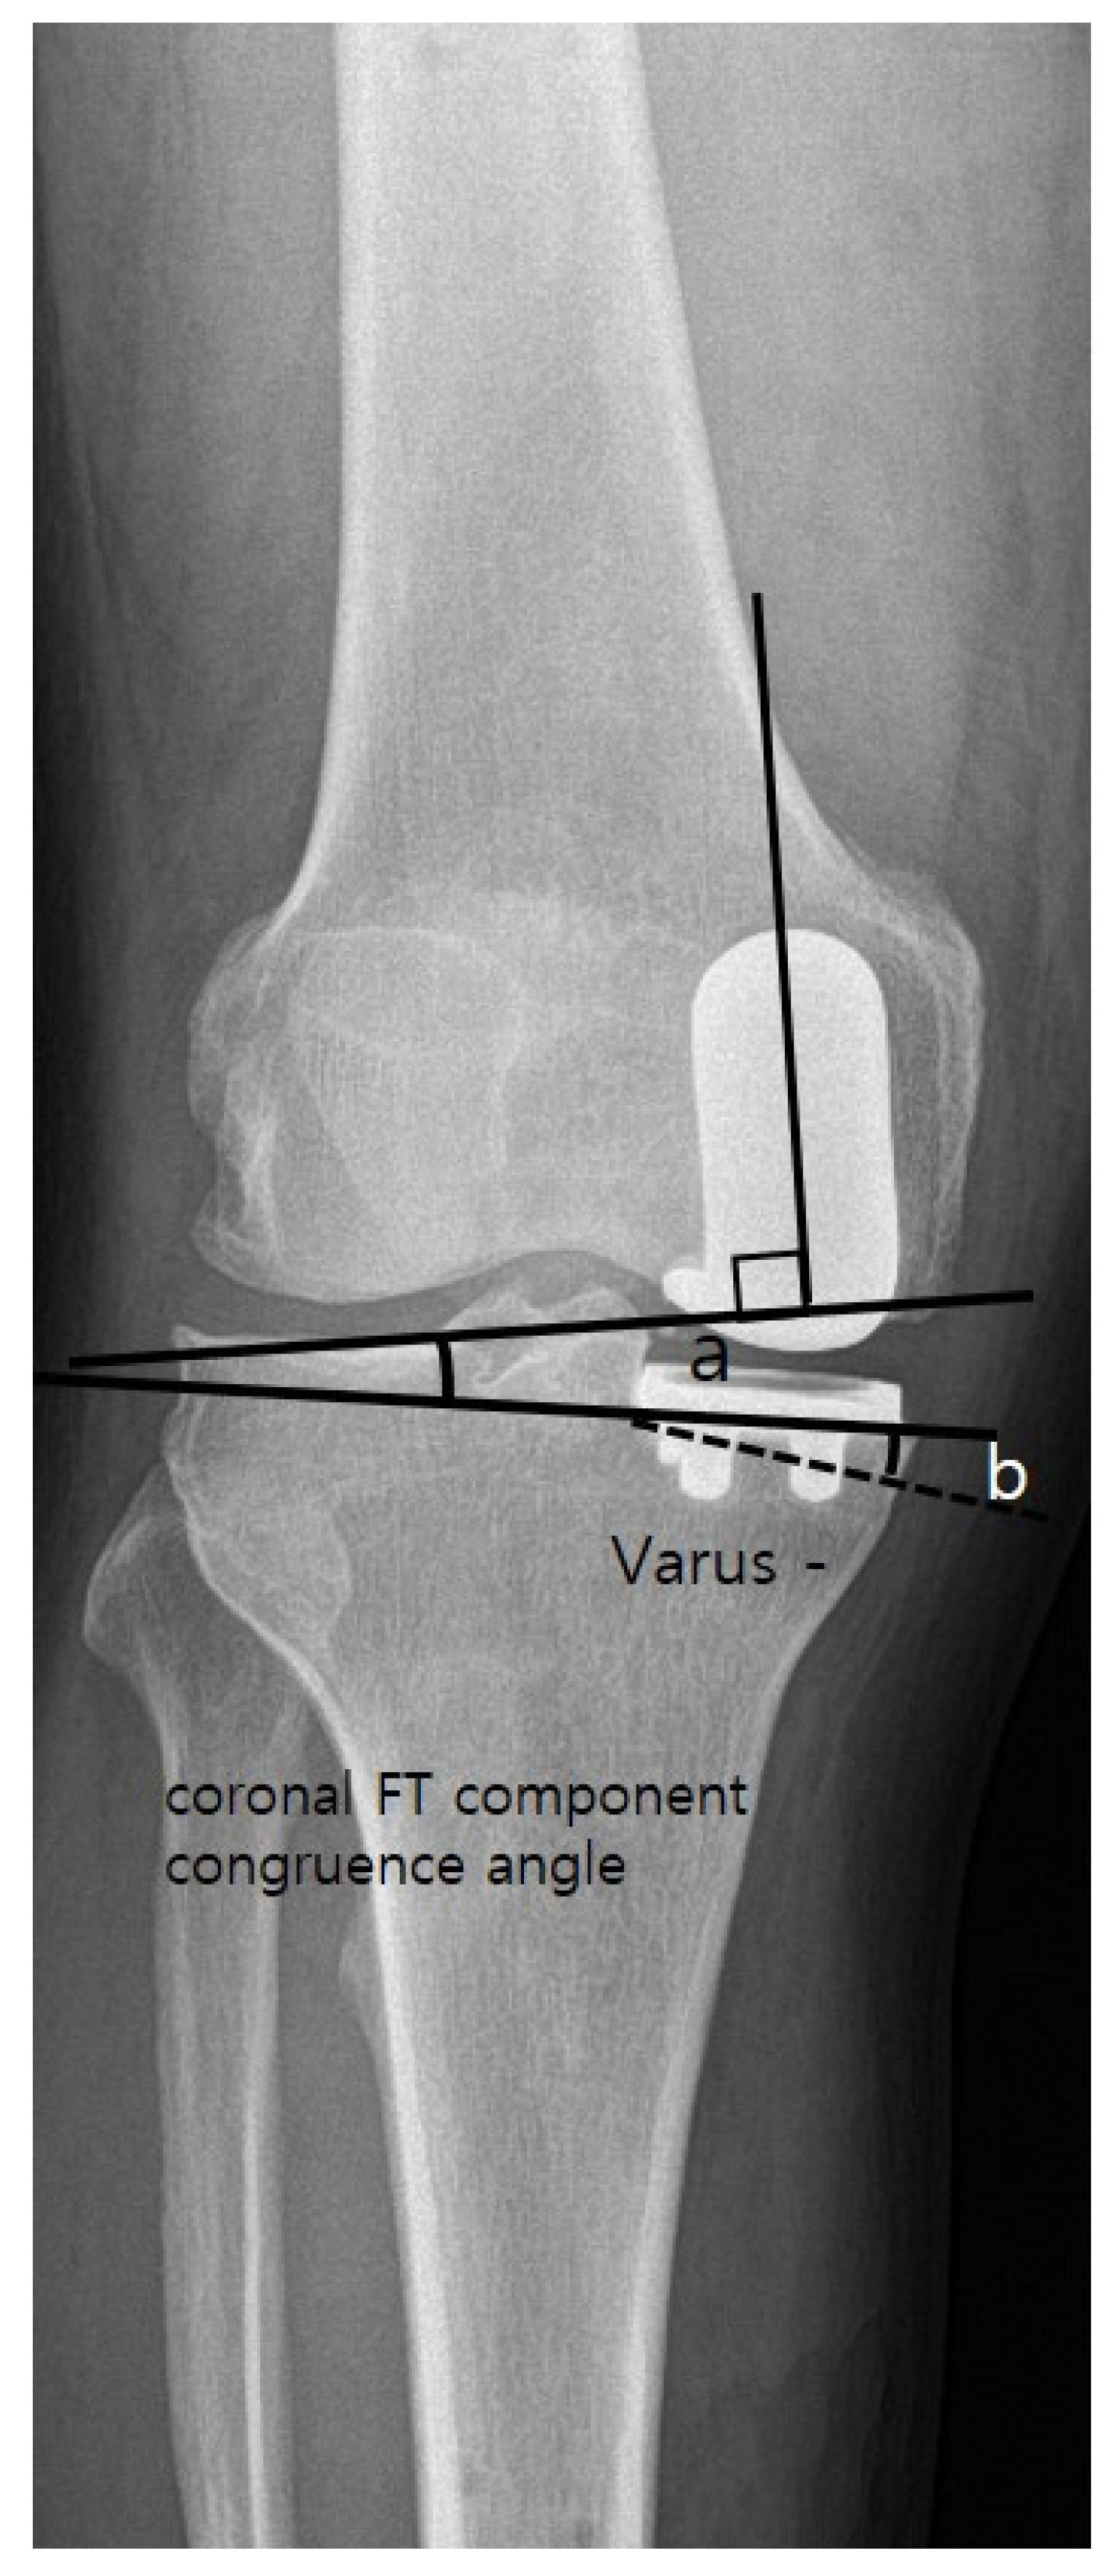

4. Clinical and Radiological Assessment

| Coronal femoral component angle (α) (°) | 2.4 ± 4.9 | −1.1 ± 3.2 | <0.001 |

| Coronal tibial component angle (β) (°) | −1.0 ± 4.3 | −3.0 ± 2.4 | 0.001 |

| Coronal FT component congruence angle (°) | 3.4 ± 4.5 | 1.9 ± 2.6 | 0.028 |